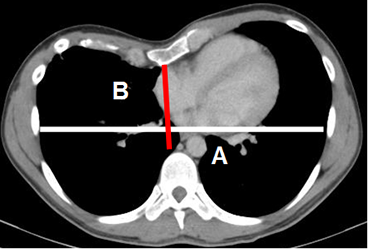

La TAC permite evaluar la severidad de esta alteración, mediante un índice. Se mide la relación entre el diámetro transverso del tórax y el anteroposterior, que normalmente es 2.56 ± 0.35. La corrección quirúrgica está indicada con un índice mayor de 3.25. (4). (Fig 18 y 19).

Fig 19. Pectum excavatum.

TAC axial. Indice de severidad. Indicación quirúrgica si la relación A/B es mayor de 3.25.

A línea blanca y B línea roja.